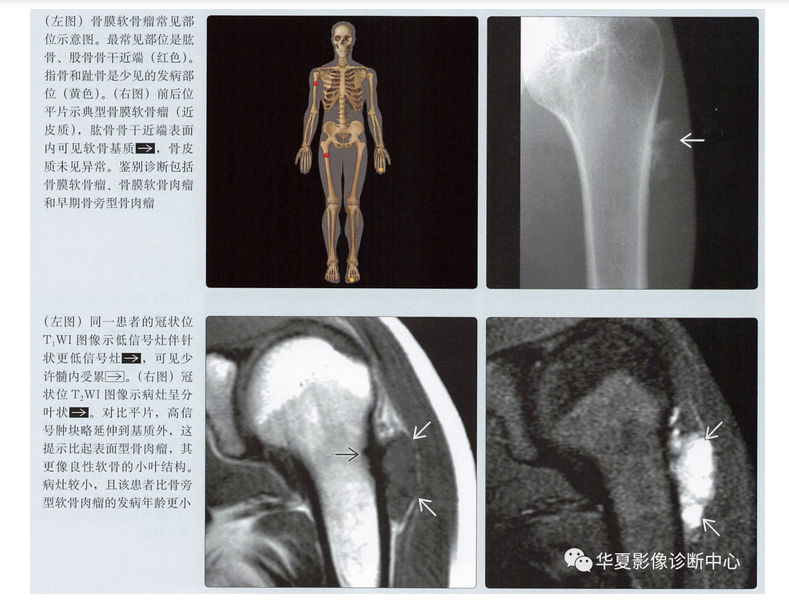

- 发病部位

- 干骺端,源于骨表面

- 肱骨或股骨近端(70%)

- 指骨或趾骨(25%)(手>足)

平片表现

- 骨皮质扇形凹陷

- 硬化边

- 致密性骨膜反应,尤其是在病灶近端、远端

- 病灶远端、近端骨皮质杯状改变

- 基质钙化(75%)

- 软组织肿块